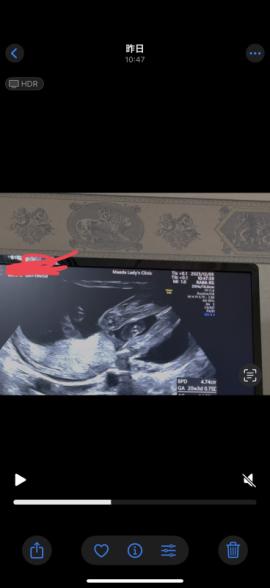

21週になりました!

ですが、まだ性別がわかりません。

いつもエコー見て検索魔になってしまい。

もし分かるのであれば教えて欲しいです

なので断言はできませんが、足と足の間男の子シンボルがはっきりと映っていなそうに感じたのと割れ目が見られるようにも思いましたので、女の子の可能性があるのではと思いました。

しかしはっきりとはわからないため、また次の健診の際に先生へご確認ください。